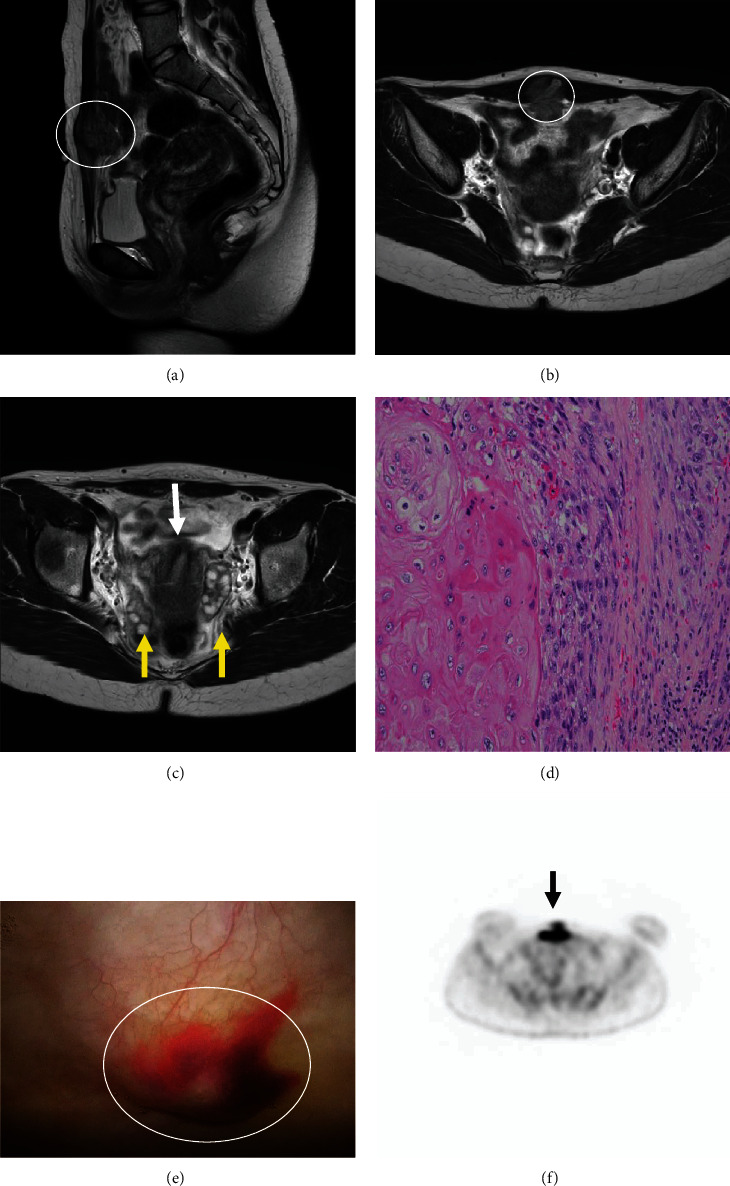

Although laparoscopic cystectomy is a safe and effective management strategy for ovarian mature cystic teratoma (MCT) in pediatric and adolescent patients, it has been challenged because of its association with a higher risk of intraoperative spillage leading to chemical peritonitis, adhesion formation, and iatrogenic implantation of malignant cells. Here, we report a rare case of a 23-year-old female patient with MCT tissue during laparoscopic ovarian cystectomy that remained in the peritoneum, possibly becoming malignant thereafter. Intraoperatively, the cyst's contents leaked into the abdominal cavity. The abdominal cavity was thoroughly cleaned before the operation was completed. Pathological examination revealed an MCT without malignant findings. The patient's postoperative course was uneventful. Although the excised tissue was benign, the patient presented with a mass at the trocar wound (upper suprapubic area) 2 years after initial surgery. Biopsy results indicated squamous cell carcinoma. Moreover, peritoneal and bladder invasions were diagnosed. She subsequently experienced symptoms of cancerous peritonitis. Achieving a complete cure through surgery alone was deemed difficult; however, successful neoadjuvant chemotherapy and tumor reduction surgery kept her alive up until the publication of this case report, 3 years since diagnosis with squamous cell carcinoma. This case indicates that malignant transformation of MCTs can occur at any age.